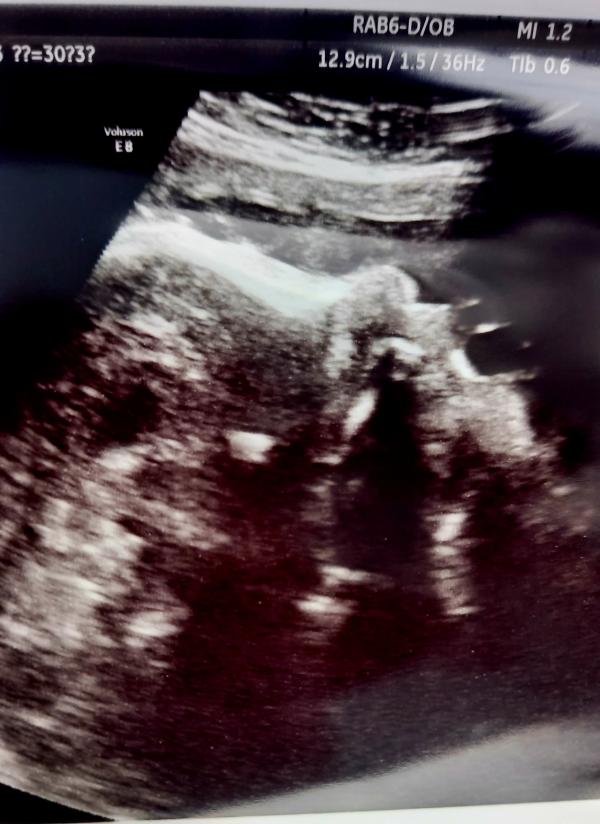

16.05.2023 ездили на УЗИ скриниг в 30 недель. Показатели в норме, 1 кг 500 грамм веса) хотели в 3д посмотреть, но малыш прикрылся пуповиной и потом уже рукой закрыл лицо. Нам еще раз подтвердили, что будет мальчик)

По фото вообще не понимаю, что изображено 🤣 где тут ребёнок, а где каля-маля. как узисты разбирают - загадка 😄

@columbia96 @yuliya01_ Это профиль вверху носик. Как нос увидешь, сразу картинка соберётся)